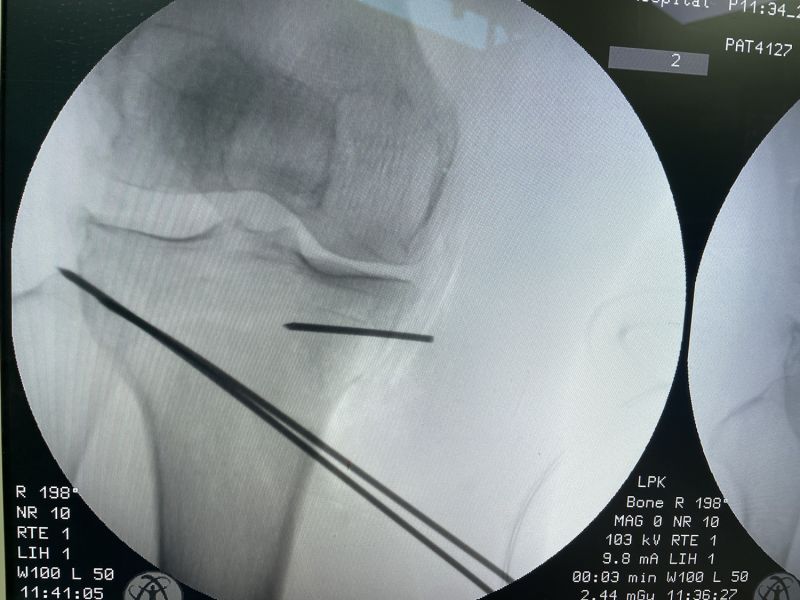

截骨术前关节镜微创清理

经过细致的术前准备,在麻醉科、手术室的大力配合下,手术团队用时一个小时就顺利完成了该手术。术中,医生对患者关节内损伤的半月板进行了修整成形,并且完成了胫骨内侧高位截骨及撑开固定,从而精准纠正患者下肢力线,将患者负重区域由膝关节内侧调整到膝关节外侧,显著改善了膝关节内侧间室疼痛的症状,患者术后第二天即可下地活动,对手术效果十分满意。